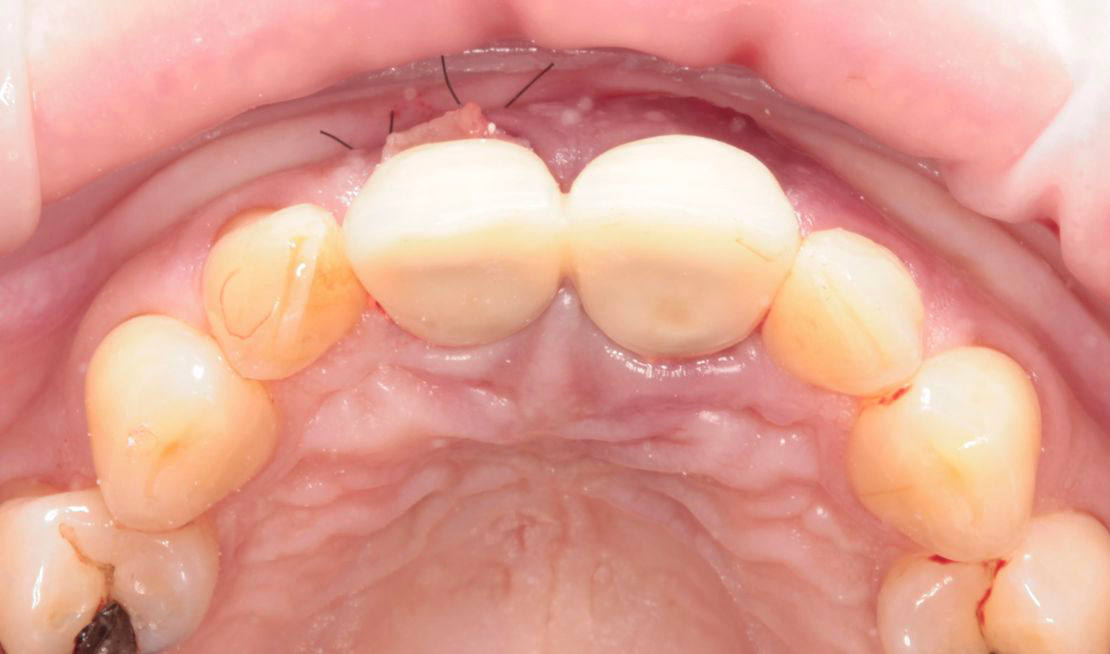

Jediným riešením bola extrakcia obidvoch zubov. Najväčšou obavou zo strany pacientky bola strata obidvoch predných zubov a následného fungovania bez nich pri práci s ľuďmi. Ideálnym riešením teda bola náhrada zubov implantátmi spolu s nasadením koruniek, a to počas jedného sedenia. V deň konzultácie bol pacientke urobený sken pomocou intraorálneho skeneru 3Shape TRIOS, ktorý nám umožňuje zobraziť 3D simuláciu ústnej dutiny. Pomocou softwaru 3Shape Implant Studio sme spojili dáta z intraorálneho skenu a CBCT, STL a DICOM súbory. V ďalšom kroku sme virtuálne vložili implantáty v správnej protetickej polohe, navrhli šablónu pre ich zavedenie, namodelovali individuálne abutmenty a korunky (obr. 4). Kompletné dáta sme exportovali pre frézovanie a 3D tlač. V laboratóriu sa pomocou 3D tlačiarne vytlačila chirurgická šablóna, ktorá nám slúži na presné zavedenie implantátov – použili sme implantačný systém Dentium Super Line. Následne boli vyfrézované zirkonové abutmenty a plastové dočasné korunky(obr. 5).

Následne sme použili protokol vŕtania a zavedenia implantátov cez šablónu (obr. 7, 8), na ktorej sme mali orientačné body pre správne napolohovanie implantátov, abutmentov a koruniek (obr. 9–14).